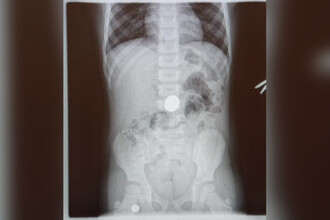

В Туапсе врачи извлекли из желудка четырехлетнего ребенка пятирублевую монету